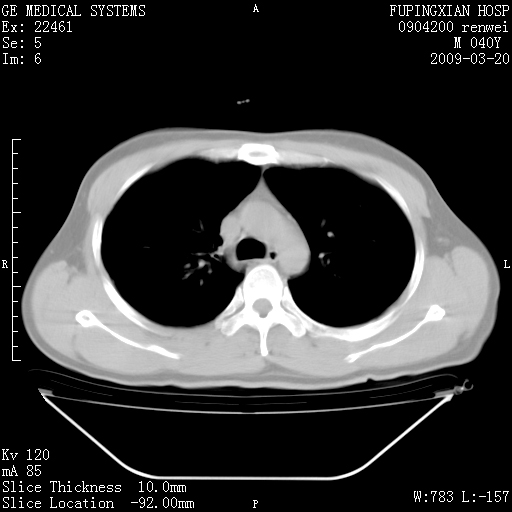

标题: CT18920:平时体健,体检时发现以下问题。 [打印本页]

标题: CT18920:平时体健,体检时发现以下问题。

单侧肺气肿表现,原因?   特发性或先天性可能

右肺气肿。

右肺局限性肺气肿

双肺弥漫磨玻样改变,肺纹理增重,考虑早期间质纤维化伴局部阻塞肺气肿,[考虑黏液栓]

双肺弥漫磨玻样改变,右肺局限性肺气肿。病人没有症状?

考虑间质性肺炎伴右侧局限性肺气肿,

先天性支气管闭锁

右肺局限性肺气肿,原因?先天支气管闭锁?粘液栓?